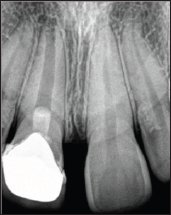

A 19year old female reported to New Al zahir Dental Clinic with chief complaint of unaesthetic appearance and pain in previously treated right upper front tooth. She gave a history of trauma 8 years ago, due to fall in house while playing with siblings and the fractured tooth segment was lost. The tooth was asymptomatic but observed tooth discoloration after 14 days of trauma. She was concerned for unaesthetic appearance and discoloration of tooth. Hence, undergone treatment by the family dentist, where pulpotomy was performed followed by aesthetic composite restoration. She was not pleased with composite restoration hence; a metal ceramic crown was provided for esthetic satisfaction. She does not recollect any sort of vitality testing done previously. She had observed an increase in gap between crown and gingiva in the first four years after placement of crown, then after its static. She is getting pain in the same tooth since 2 weeks. Clinical examination revealed, red edematous gingiva, accelerated gingival recession with round and thick gingival margin around maxillary right central incisor (Figure 1). Thermal and electric pulp testing revealed non-vitality for maxillary right central incisor. Radiographic investigation revealed an attempt for cervical pulpotomy was made but ended up presenting a periapical lesion having restricted root formation with an open apex (Figure 2).

Figure 2.